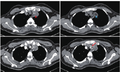

• 肺炎型肺腺癌与肺炎,如何区分?

肺炎型肺腺癌与肺炎,如何区分?

病例资料 患者男,54岁,因 发热 、 咳嗽 和呼吸急促到我院就诊,并伴全身乏力和体重减轻。患者于外院被诊断为痰检阳性 肺结核 ,过去2个月以来服用抗结核药物。 PA胸片示双肺大面